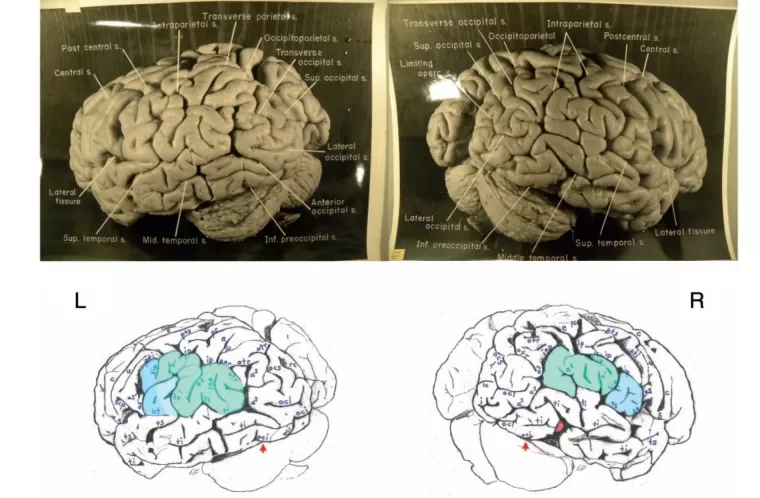

Top: Dorsal photograph of Einstein’s brain with original labels. Bottom: Our identifications. a2 = angular; a3 = anterior occipital; c = central; e = processus acuminis; fm = midfrontal; fs = superior frontal; inp = intermediate posterior parietal; ip = intraparietal; m = marginal; mf = medial frontal; ocs = superior occipital; otr = transverse occipital; par = paroccipital; pci = precentral inferior; pcs = precentral superior; pma = marginal precentral; pme = medial precentral; po = parieto-occipital; prc = paracentral; ps = superior parietal; pst = transverse parietal; pti = postcentral inferior; pts = postcentral superior; rc = retrocalcarine; u = unnamed. k = presumed motor cortex for right hand; K = ‘knob’ representing motor cortex for left hand. In both hemispheres, e limits anteriorly the first annectant gyrus, a pli de passage of Gratiolet that connects the parietal and occipital lobes, indicated by red arrows (see also Fig. 7). This figure is reproduced with permission from the National Museum of Health and Medicine.Top: Photographs of the left (L) and right (R) lateral surfaces of Einstein’s brain taken with the front of the brain rotated toward the viewer, with original labels. Bottom: Our identifications. Numbers 1–4 indicate four gyri in Einstein’s right frontal lobe, rather than three as is typical; K = ‘knob’ representing motor cortex for left hand. Submerged gyri are shaded red near the diagonal sulcus on each side. It is clear from the left hemisphere that the posterior ascending limb of the Sylvian fissure and the postcentral inferior sulcus are not confluent, contrary to the literature. Sulci: a = additional inferior frontal; a1 = ascending branch of the superior temporal sulcus; a2 = angular; aS = posterior ascending limb of the Sylvian; c = central; d = diagonal; dt = descending terminal branch of the Sylvian; fi = inferior frontal; fm = midfrontal; fs = superior frontal; ht = posterior terminal horizontal branch of the Sylvian; ip = intraparietal; mf = medial frontal; pci = precentral inferior; pcs = precentral superior; pma = marginal precentral; pti = postcentral inferior; pts = postcentral superior; R = ascending ramus of anterior Sylvian fissure; R’ = horizontal ramus of anterior Sylvian fissure; S = Sylvian fissure; sa = sulcus acousticus; sca = subcentral anterior; scp = subcentral posterior; sip = intermedius primus of Jensen; ti = inferior temporal; tri = triangular; ts = superior temporal; tt = transverse temporal; u = unnamed; W = fronto-marginal of Wernicke. 1 = superior frontal gyrus; 2 = atypical superior middle frontal gyrus; 3 = atypical inferior middle frontal gyrus; 4 = inferior frontal gyrus (usually the ‘inferior third frontal gyrus’). The figure reproduced with permission from the National Museum of Health and Medicine.Top: Photographs of the left (L) and right (R) lateral surfaces of Einstein’s brain taken from a traditional view, which lack original labels. Bottom: Our identifications. Numbers 1–4 on the right hemisphere indicate four gyri in Einstein’s right frontal lobe, rather than three as is typical. Sulci: a = additional inferior frontal; a1 = ascending branch of the superior temporal sulcus; a2 = angular; a3 = anterior occipital; aS = posterior ascending limb of the Sylvian; c = central; d = diagonal; dt = descending terminal branch of the Sylvian; e = processus acuminis; fi = inferior frontal; fm = midfrontal; fs = superior frontal; ht = posterior terminal horizontal branch of the Sylvian; inp = intermediate posterior parietal; ip = intraparietal; mf = medial frontal; ocl = lateral occipital; ocs = superior occipital; otr = transverse occipital; par = paroccipital; pci = precentral inferior; pcs = precentral superior; ps = superior parietal; pti = postcentral inferior; pts = postcentral superior; R = ascending ramus of anterior Sylvian fissure; R’ = horizontal ramus of anterior Sylvian fissure; S = Sylvian fissure; sa = sulcus acousticus; sca = subcentral anterior; scp = subcentral posterior; sip = intermedius primus of Jensen; ti = inferior temporal; tri = triangular; ts = superior temporal; tt = transverse temporal; u = unnamed. 1 = superior frontal gyrus; 2 = atypical superior middle frontal gyrus; 3 = atypical inferior middle frontal gyrus; 4 = inferior frontal gyrus (usually the ‘inferior third frontal gyrus’). K = ‘knob’ representing motor cortex for left hand. The figure is reproduced with permission from the National Museum of Health and Medicine.Top: Photographs of the left (L) and right (R) lateral surfaces of Einstein’s brain taken with the back of the brain rotated towards the viewer, with original labels. Bottom: Our identifications. The arrows indicate the pre-occipital notch at the inferolateral border of each hemisphere, which indicate the approximate inferior boundary between the lateral surfaces of the temporal and occipital lobes; on the right, an apparent artificial cut severed the rostral tip (shaded red) of a gyrus in the posterior part of the inferior temporal lobe. This cut appears to be a lateral extension of that observed on the right side of the base of the brain (Fig. 6). Typically, the supramarginal gyrus surrounds the posterior ascending limb of the Sylvian, and the angular gyrus surrounds the upturned end(s) of superior temporal sulcus. These gyri are separated approximately at the level of the intermedius primus sulcus of Jensen and together form the inferior parietal lobule. The supramarginal gyri are shaded blue; the angular gyri are aqua. In the left hemisphere, part of the cortical region above posterior terminal horizontal branch of the Sylvian is shaded an inbetween colour because it could arguably belong to either gyrus. Einstein’s inferior parietal lobules have different shapes in the two hemispheres, and appear to be relatively larger on the left side. Sulci: a1 = ascending branch of the superior temporal sulcus; a2 = angular; a3 = anterior occipital; aS = posterior ascending limb of the Sylvian; c = central; dt = descending terminal branch of the Sylvian; e = processus acuminis; ht = posterior terminal horizontal branch of the Sylvian; i = inferior polar; inp = intermediate posterior parietal; ip = intraparietal; lc = lateral calcarine; oci = inferior occipital; ocl = lateral occipital; ocs = superior occipital; otr = transverse occipital; par = paroccipital; ps = superior parietal; pti = postcentral inferior; pts = postcentral superior; rc = retrocalcarine; S = Sylvian fissure; scp = subcentral posterior; sip = intermedius primus of Jensen; ti = inferior temporal; ts = superior temporal; u = unnamed. The figure is reproduced with permission from the National Museum of Health and Medicine.Top: Photograph of a frontal view of Einstein’s brain in an unconventional orientation, with original labels. Bottom: Our identifications of sulci. a = additional inferior frontal; fi = inferior frontal; fm = midfrontal; fs = superior frontal; mf = medial frontal; S = Sylvian fissure; ts = superior temporal; W = fronto-marginal of Wernicke. The figure is reproduced with permission from the National Museum of Health and Medicine.Top: Separate photographs of the right (R) and left (L) basal views of Einstein’s bisected brain with cerebellum removed and original labels. Bottom: Our identifications. The two photographs are not to the same scale and the right hemisphere is rotated slightly laterally compared with the left, as suggested by a published basal photograph of the entire brain with its cerebellum attached (Witelson et al., 1999b). The base of Einstein’s brain appears to have been accidentally cut, perhaps with a scalpel, as indicated in red shading. This may have occurred during removal of the dura mater (tentorium cerebelli) that separates the dorsum of the cerebellum from the inferior surface of the occipital lobes. Magnifying the photographs on a computer screen should facilitate observation of these cuts. See Fig. 4 for an extension of this cut that reached the right lateral surface of the temporal lobe where it severed the tip of a gyrus (shaded in red). Sulci: arc = arcuate orbital; col = collateral; fi = inferior frontal; i = inferior polar; mo = medial orbital; oa = anterior orbital; oal = lateral anterior orbital; oci = inferior occipital; oct = occipito-temporal; op = posterior orbital; opl = lateral posterior orbital; os = olfactory; R’ = horizontal ramus of anterior Sylvian fissure; rh = rhinal; ti = inferior temporal. Abbreviations of other features: los = lateral olfactory stria; mb = mammillary body; mos = medial olfactory stria; ob = olfactory bulb; on = optic nerve; ot = olfactory tract. The figure is reproduced with permission from the National Museum of Health and Medicine.Top: Photograph of an occipital view of Einstein’s brain in an unconventional orientation, with original labels. Bottom: Our identifications. In both hemispheres, a processus acuminis limits anteriorly the first annectant gyrus, a pli de passage of Gratiolet that connects the parietal and occipital lobes, indicated by red arrows (see also Fig. 1). See Fig. 10B for shading of the superior and inferior parietal lobules and the occipital lobe on this image. Sulci: a2 = angular; a3 = anterior occipital; c = central; cu = cuneus; e = processus acuminis; inp = intermediate posterior parietal; ip = intraparietal; lc = lateral calcarine; m = marginal; oci = inferior occipital; ocl = lateral occipital; ocs = superior occipital; otr = transverse occipital; par = paroccipital; pcs = precentral superior; po = parieto-occipital; ps = superior parietal; pst = transverse parietal; pti = postcentral inferior; pts = postcentral superior; rc = retrocalcarine; sp = subparietal; ss = superior sagittal; ti = inferior temporal; ts = superior temporal. The figure is reproduced with permission from the National Museum of Health and Medicine.Top: Photographs of the left (L) and right (R) medial surfaces of Einstein’s brain with original labels. Bottom: Our identifications. Arrows indicate sulci that extend onto the dorsolateral surface of the brain. Sulci: ac = anterior calcarine; apo = anterior parolfactory; c = central; ca = callosal; cal = calcarine; ci = cingulate; cu = cuneus; li = lingual; lp = limiting sulcus of precuneus; m = marginal; mf = medial frontal; otr = transverse occipital; pc = paracalcarine; pma = marginal precentral; pme = medial precentral; po = parieto-occipital; prc = paracentral; pst = transverse parietal; rc = retrocalcarine; ri = inferior rostral; rs = superior rostral; si = inferior sagittal; sp = subparietal; ss = superior sagittal; u = unnamed. Other abbreviations: cc = corpus callosum; f = fornix; hpt = hypothalamus; ipo = parieto-occipital incisure; sep = septum pellucidum; th = thalamus. See text for discussion. The figure is reproduced with permission from the National Museum of Health and Medicine.Top: Photograph of Einstein’s right insula after removal of the opercula, with original labels. Bottom: Our identifications of sulci: aps = anterior periinsular; cis = central insular; pcis = precentral insular; pis = postcentral insular; sis = short insular; sps = superior periinsular; Other identification: ia = apex of insula. The figure is reproduced with permission from the National Museum of Health and Medicine.